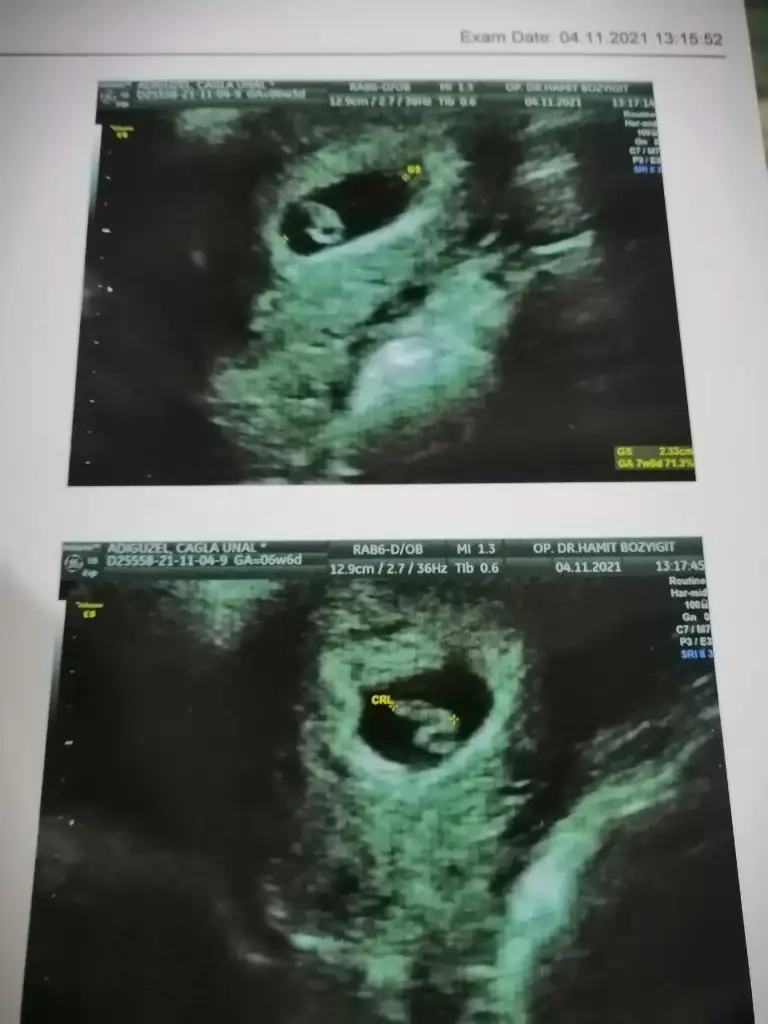

Canım kaçıncı haftadasn senManyakPrenses canım merhaba ultrason cinsiyet için tahminin ne bakarmısın benim için birde kalp atışı dk 143 çıktı çok şükür kalp atışı gördük

6+6 haftalık gözüktü bugün aslında 6+3 bebek önden gidiyormuşCanım kaçıncı haftadasn sen

Canım kese fasulye gibi erkeğe benzettim benManyakPrenses canım merhaba ultrason cinsiyet için tahminin ne bakarmısın benim için birde kalp atışı dk 143 çıktı çok şükür kalp atışı gördük